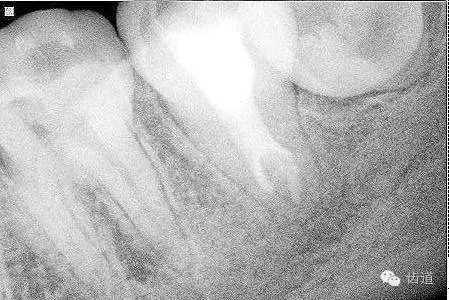

2. 術(shù)后半年X線檢查,可見根尖周膜連續(xù)性恢復(fù),根尖周透射影消失